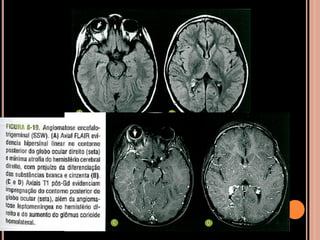

SÍNDROME DE STURGE WEBER(SSW)

SÍNDROME DE STURGE-WEBER

 Angiomatose encéfalo trigeminal;

 Congênita rara; Considerada a princípio como

esporádica;

 Angiomatose venosa leptomeníngea, lesão

cutânea facial ispsilateral que coincide com o

território do trigêmio, envolvendo pelo menos sua

porção oftálmica; depósitos de cálcio cerebrais;

 Lesões cutâneas: veias dilatadas ou

telangiectasias que contêm sangue desoxigenado

apresentando a cor de “vinho do Porto” do nevo

facial;

 Manchas cutâneas isoladas  nevo comum;

 Condição para dx de SSW  lesão intracraniana

com ou sem nevo facial;

 Ocular: angioma da corioide, risco aumentado de

glaucoma;

 Manifestações intracranianas: região de drenagem

venosa anormal e circulação colateral;

 Pode haver recrutamento de veias medulares para

drenagem do córtex (alteração angiomatosa de

plexo corioide aumenta dimensões e

vascularização);

 Circulação anormal  atrofia do parênquima

adjacente;

 Isquemia cerebral crônica –atrofia cortical

lentamente progressiva com calcificações

distróficas girais;

Crises epilépticas Retardo mental

Nevo facial de cor do

“vinho do Porto”

 Nevo presente desde o nascimento e localiza-se

no dermátono do nervo trigêmio;

 Principalmente crises epilépticas: devido à

circulação anormal;

 Atraso no desenvolvimento...